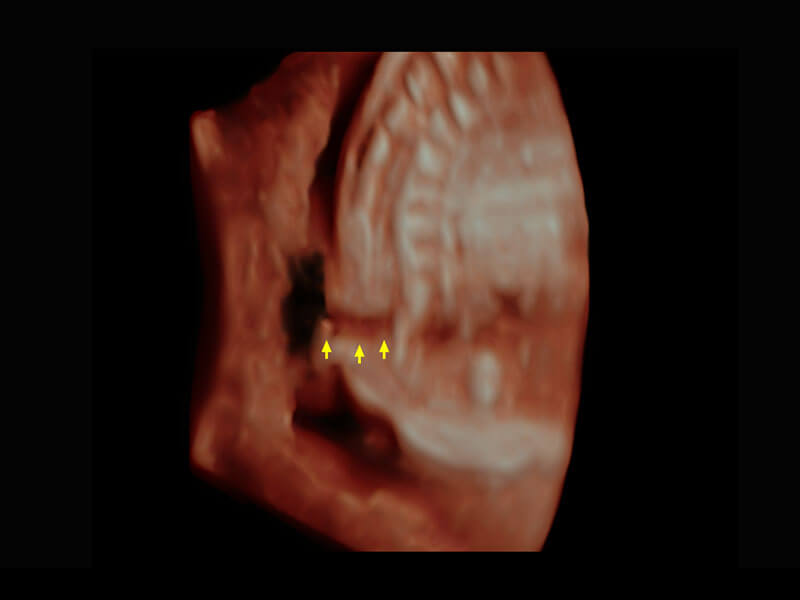

P60在胎儿早孕期超声筛查中为您带来优异的图像质量。

光影成像-孕囊